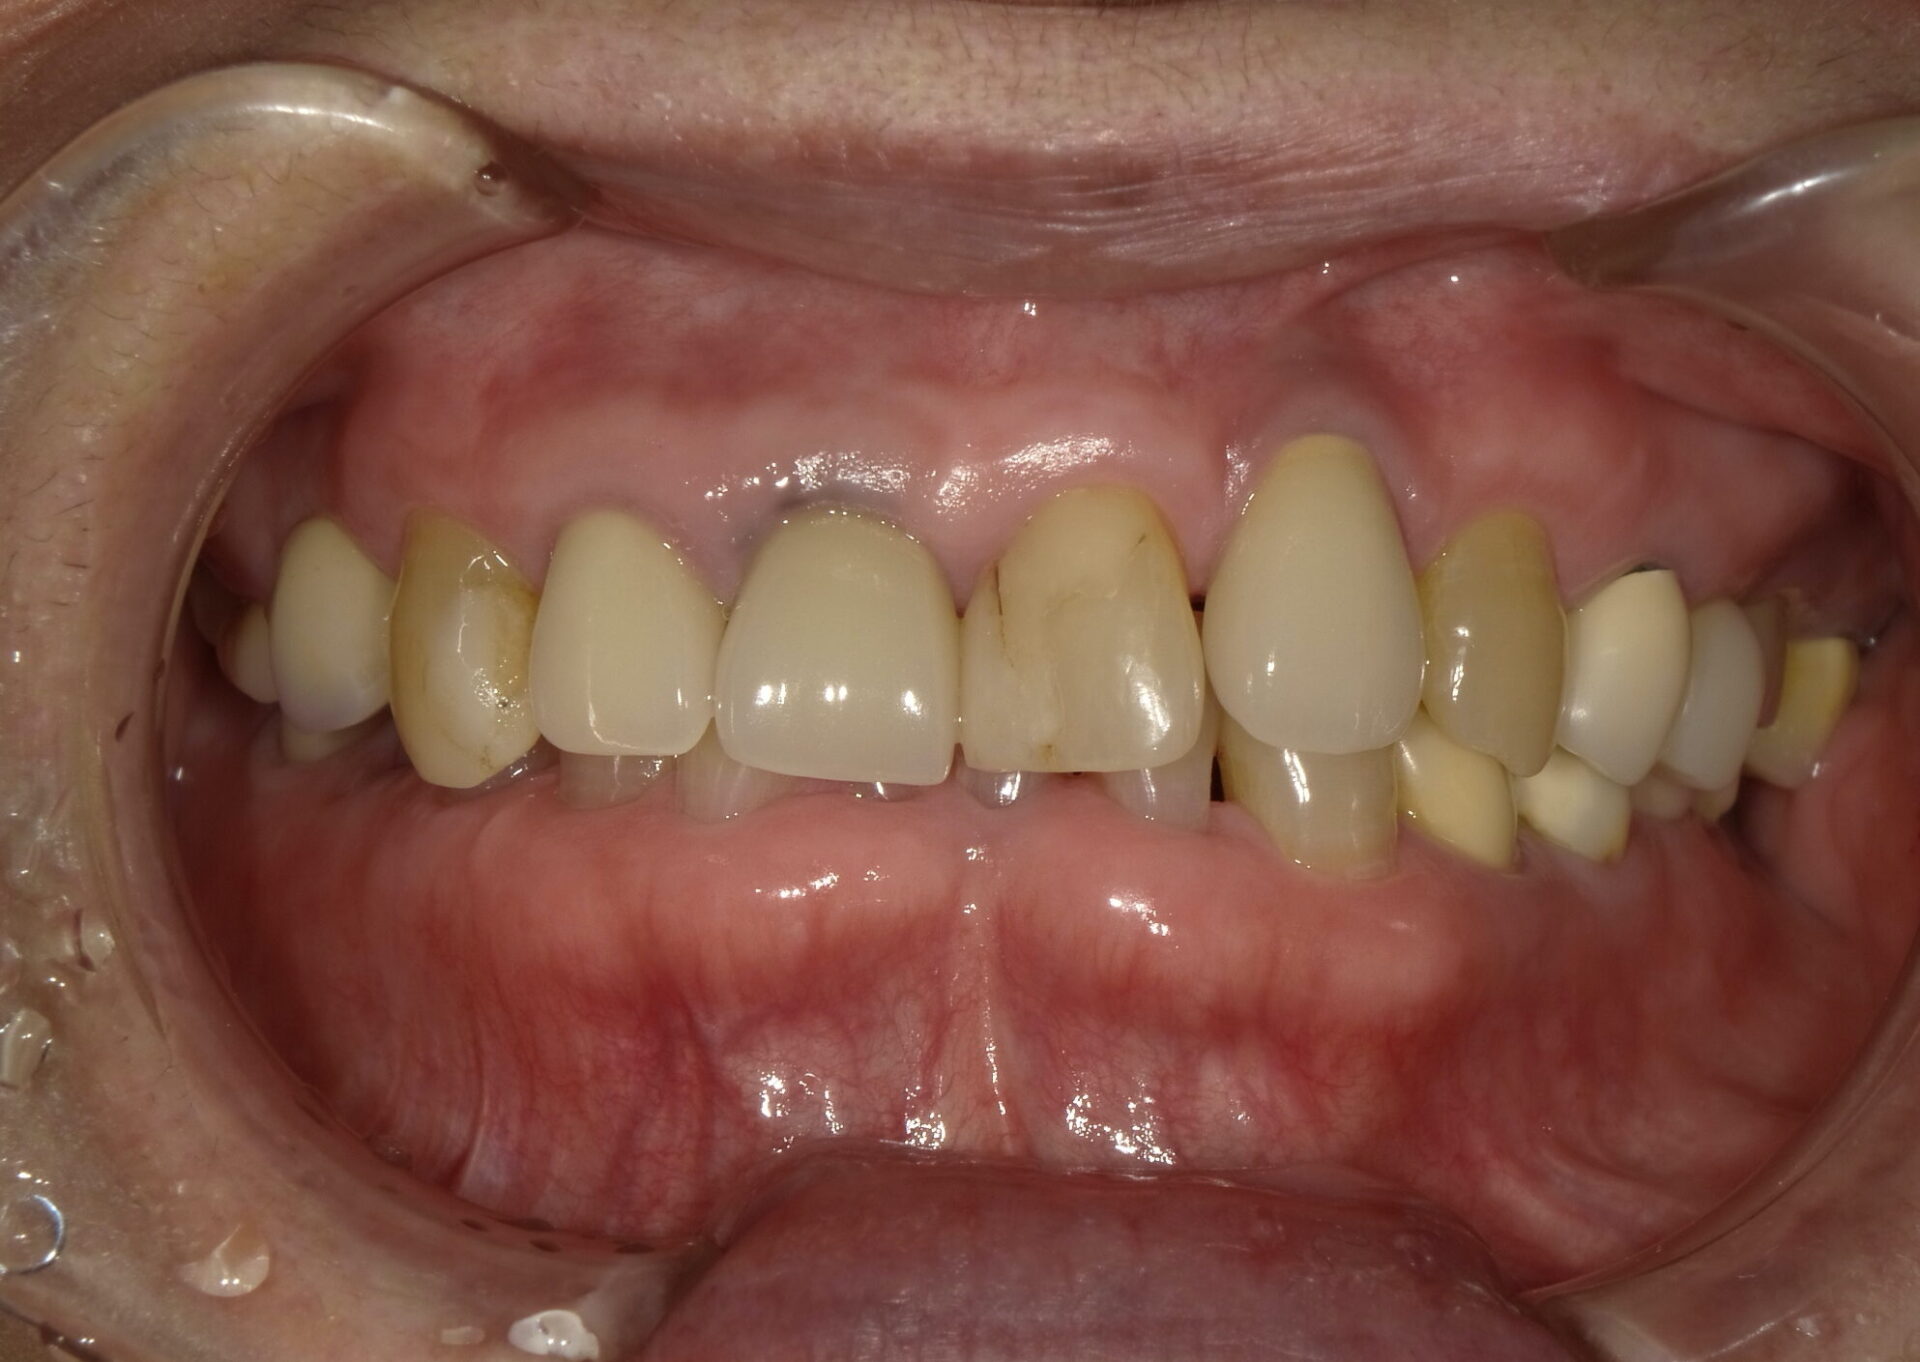

不正咬合の種類

叢生・八重歯 (ガタガタの歯並び)

正しい位置に歯が生えるためのスペースが不足している歯並びです。 歯と歯が重なりあっていたり、八重歯や乱杭歯になっている状態を叢生(そうせい)といいます。

偏位(歯の歪み・ずれ)

上あごと下あごの真ん中(正中)があっていない歯並びを「偏位(へんい)」といいます。 骨格のズレや顎関節の左右差、歯並びの左右の非対称など、さまざまな原因が考えられます。